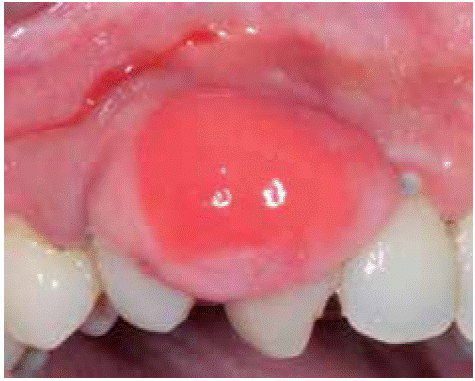

Case 3

A systemically healthy, 29 year old female sought consultation due to a three year old gingival lesion located at the anterior sector of the upper jaw. Patient reported lesion onset during her pregnancy, and progressive lesion growth without presence of pain. Clinical evaluation revealed a soft, mobile, pedicled tumor, approximately measuring 20 X 16 mm located at the level of teeth 23 and The tumor was of a pinkish hue and exhibited keratinization foci (Figure 17). Periodontal assessment revealed periodontal pockets and a 78% oral hygiene index (O'Leary). Radiographic examination showed interproximal calculus in the gingival lesion area (Figure 18).